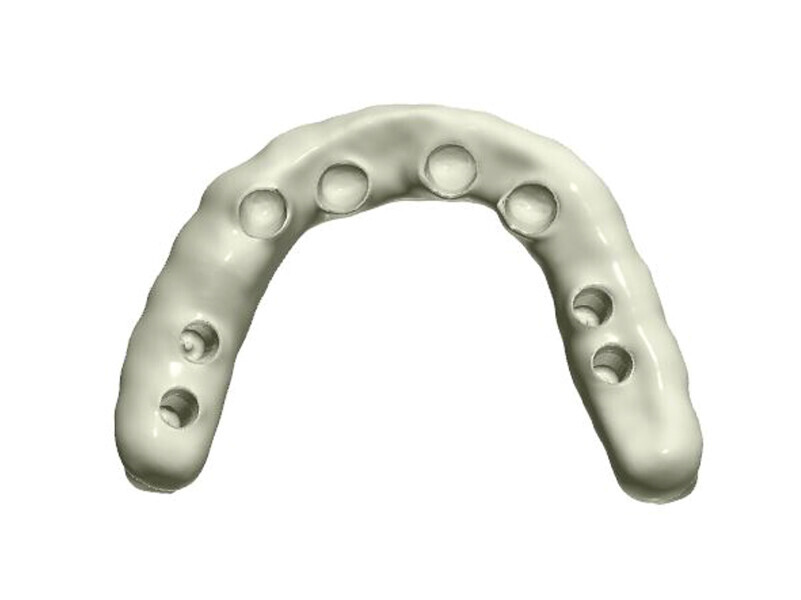

Fig. 5: Design of the framework visible from the palatal side. Visible abutments prior to the placement of telescopic crowns at the frontal section with abutments to be attached by

means of screws at the lateral section.